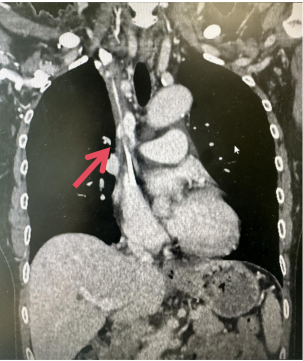

右側長期血透管內及周圍大量血栓

左側中心靜脈閉塞